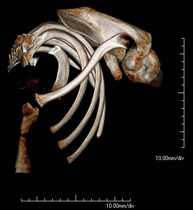

- Ribcage CT

Utilising an X-ray system and detectors that rotate around a patient, this radiological scan generates images that are computer-reconstructed to facilitate a close examination of the ribcage.